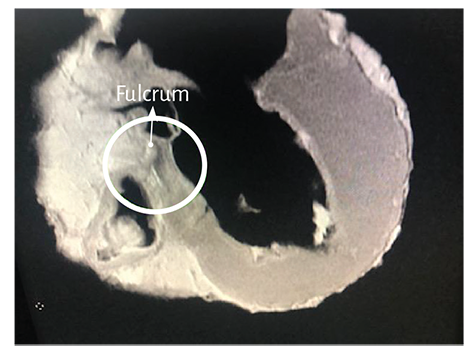

Figure 1.18. The figure shows the ascending segment, which is going to insert in the cardiac fulcrum (bovine heart) (see Figure 1.19).

The macroscopic and microscopic observation reveal the muscle fiber attachment to this solid, homogeneous nucleus, which is closely related with the aortic wall on the side of the tricuspid valve. Its configuration has been confirmed histologically. We have called his structure, origin and end of the myocardial band, cardiac fulcrum, as a parallelism and tribute to the definition of the supporting point of a lever expressed by Archimedes of Syracuse (Greek, 288 B.C. – 212 B.C.). It is located anterior to the central fibrous ridge (right trigone) and it clearly shows that the myocardial fibers of the right segment originate in its structure (Figure 1.16) same as the ascending segment courses to meet it in order to attach (Figures 1.18 and 1.19). It should be noted that to visualize the cardiac fulcrum it is essential to unfold the myocardial band. This osseous, cartilaginous or tendinous structure was always present and with the same morphology in all the hearts analyzed by us, albeit with different histological texture. No description of its characteristics or function has been reported in the literature, except the mere mention of its presence as os cordis in bovids.